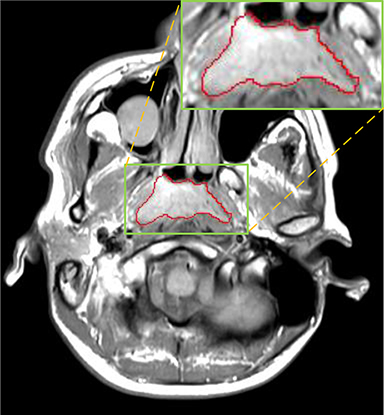

Some typical predicted results of MMFNet are visualized in Figure 12. And it is worth mentioning that our proposed network is extremely time-friendly compared to manually marking by radiologists. Specifically speaking, our proposed method only needs about 9s to realize NPC delineation of a patient, while an experienced radiologist needs 10 to 20 minutes to complete it.

Refer to caption

(a) left view

(b) front view

(c) right view

Figure 12: Some visualization examples of MMFNet’ predicted results, purple regions are NPC regions.